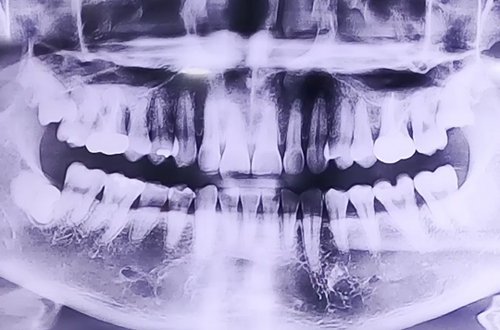

왼쪽 위 부러진 어금니 임플란트

AFTER

X-ray 상에서는 치아에 큰 이상이 없어 보였지만 치아를 자세히 검사해 보니 왼쪽 위 어금니가 반으로 쪼개진 상태로 발치 이후 즉시 임플란트 치료를 진행하였고 뼈가 비어있는 부분들은 임플란트 주변 뼈이식을 진행해 드리면서 마무리해드렸습니다.

현재는 임플란트 위로 치아머리를 만들기 위한 부품을 끼워 놓은 상태이며 추후 임플란트가 단단히 자리 잡고 난 뒤 보철이 완성되면 다음 진료일지로 찾아뵙도록 하겠습니다! ^^